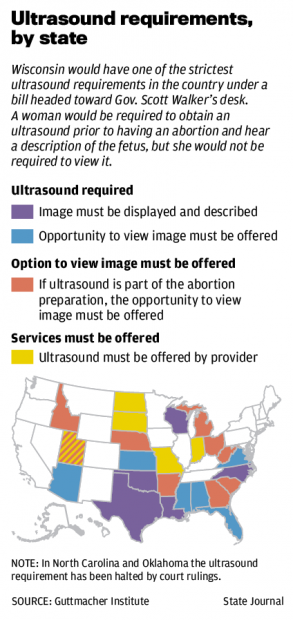

State Micaiah Bilger Jun 17 2020 914AM Des Moines IA. Planned Parenthood Takes Aim at Indiana Ultrasound Law Tim Bradley November 16 2016. Doctors in Planned Parenthood and other abortion clinics use ultrasounds to determine the age and size of the baby or to guide them as they perform abortions.

A federal judge heard arguments on November 9 on Planned Parenthoods challenge to an Indiana law requiring that an ultrasound be performed on a woman seeking an abortion at least 18 hours before the abortion is scheduled to take place. From the information I have read Planned Parenthood uses ultrasound for the abortion procedure they will not perform an ultrasound for someone wantingintendingconsidering keeping their baby. No they do not.

20 that Planned Parenthood has conceded defeat in a lawsuit that challenged a state law requiring women to undergo an ultrasound at least. Planned Parenthood continues to perpetuate the myth that it offers the comprehensive healthcare women need not simply abortions. Your doctor might also be able to help you find affordable ultrasounds in your area.

Planned Parenthood uses ultrasound to determine a babys age and position in the womb before it kills her. They rarely use them otherwise. ADVERTISEMENT The abortion business is criticizing an Iowa bill that ensures abortion facilities give women the opportunity to see their unborn babies on an ultrasound and hear their babys heartbeat at least 24 hours prior to.